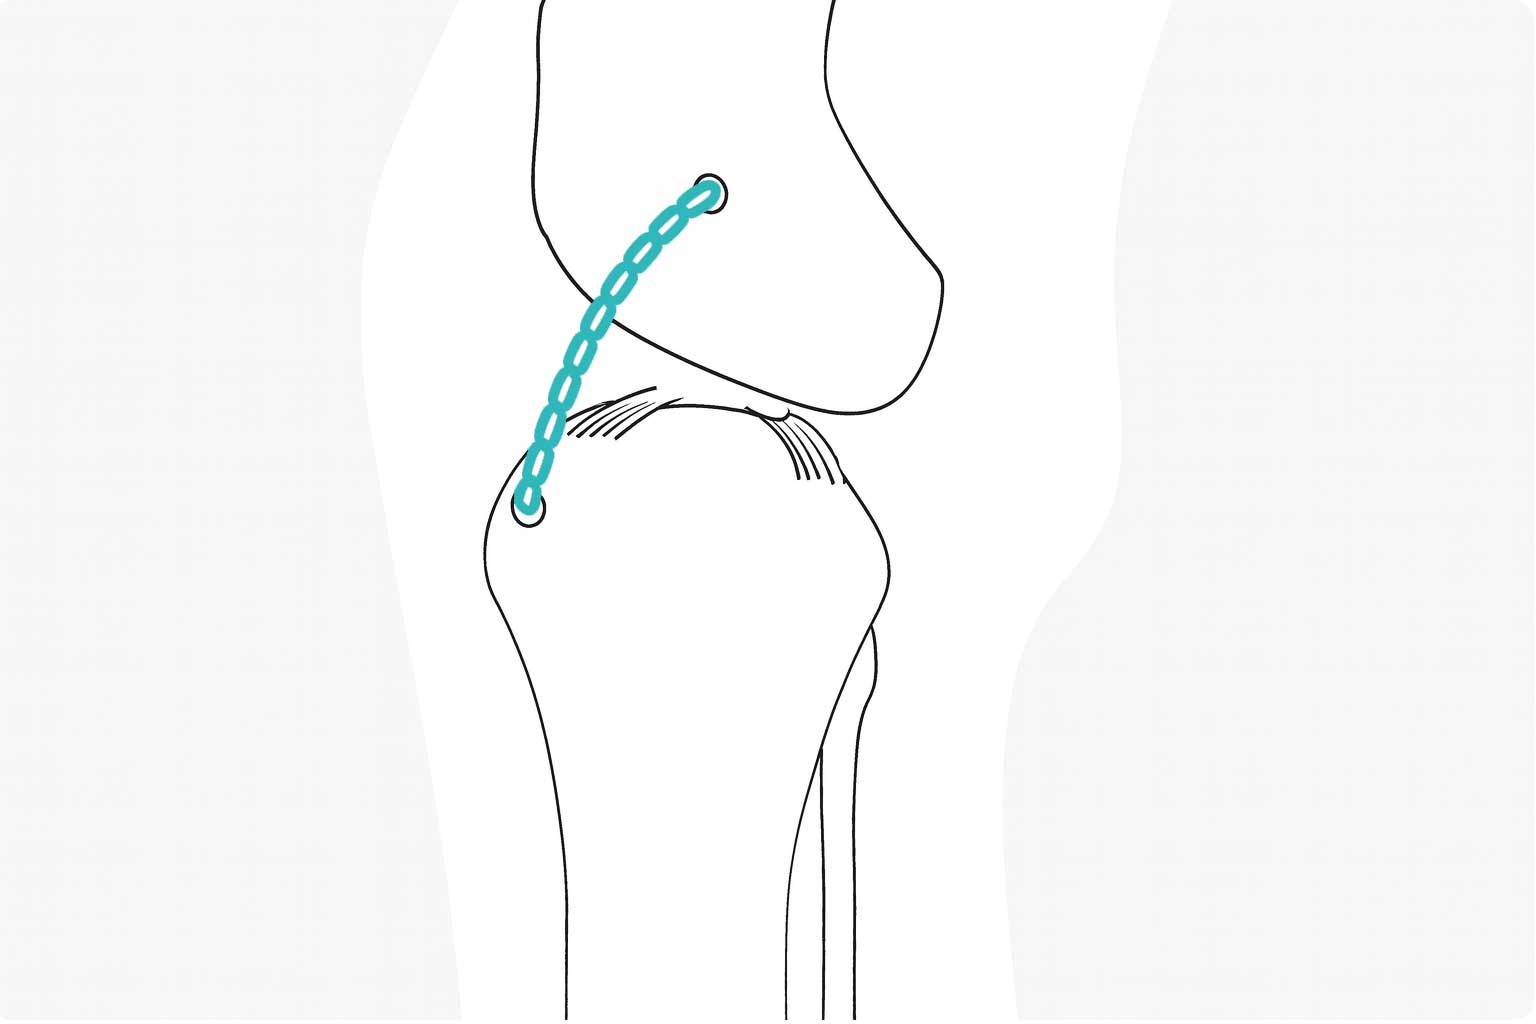

전십자인대 단열 위치 이미지

ECS Extra Capsular Suture

낭외고정법은 전십자인대의 역할을 인공인대를 통하여 일정시간 유지함으로서 무릎관절의 기능을 회복할 수 있도록 도움을 주는 방법입니다. 뼈자름술에 비하여 덜 침습적이며 소형견에서 많이 적용되는 수술법 중 하나입니다.